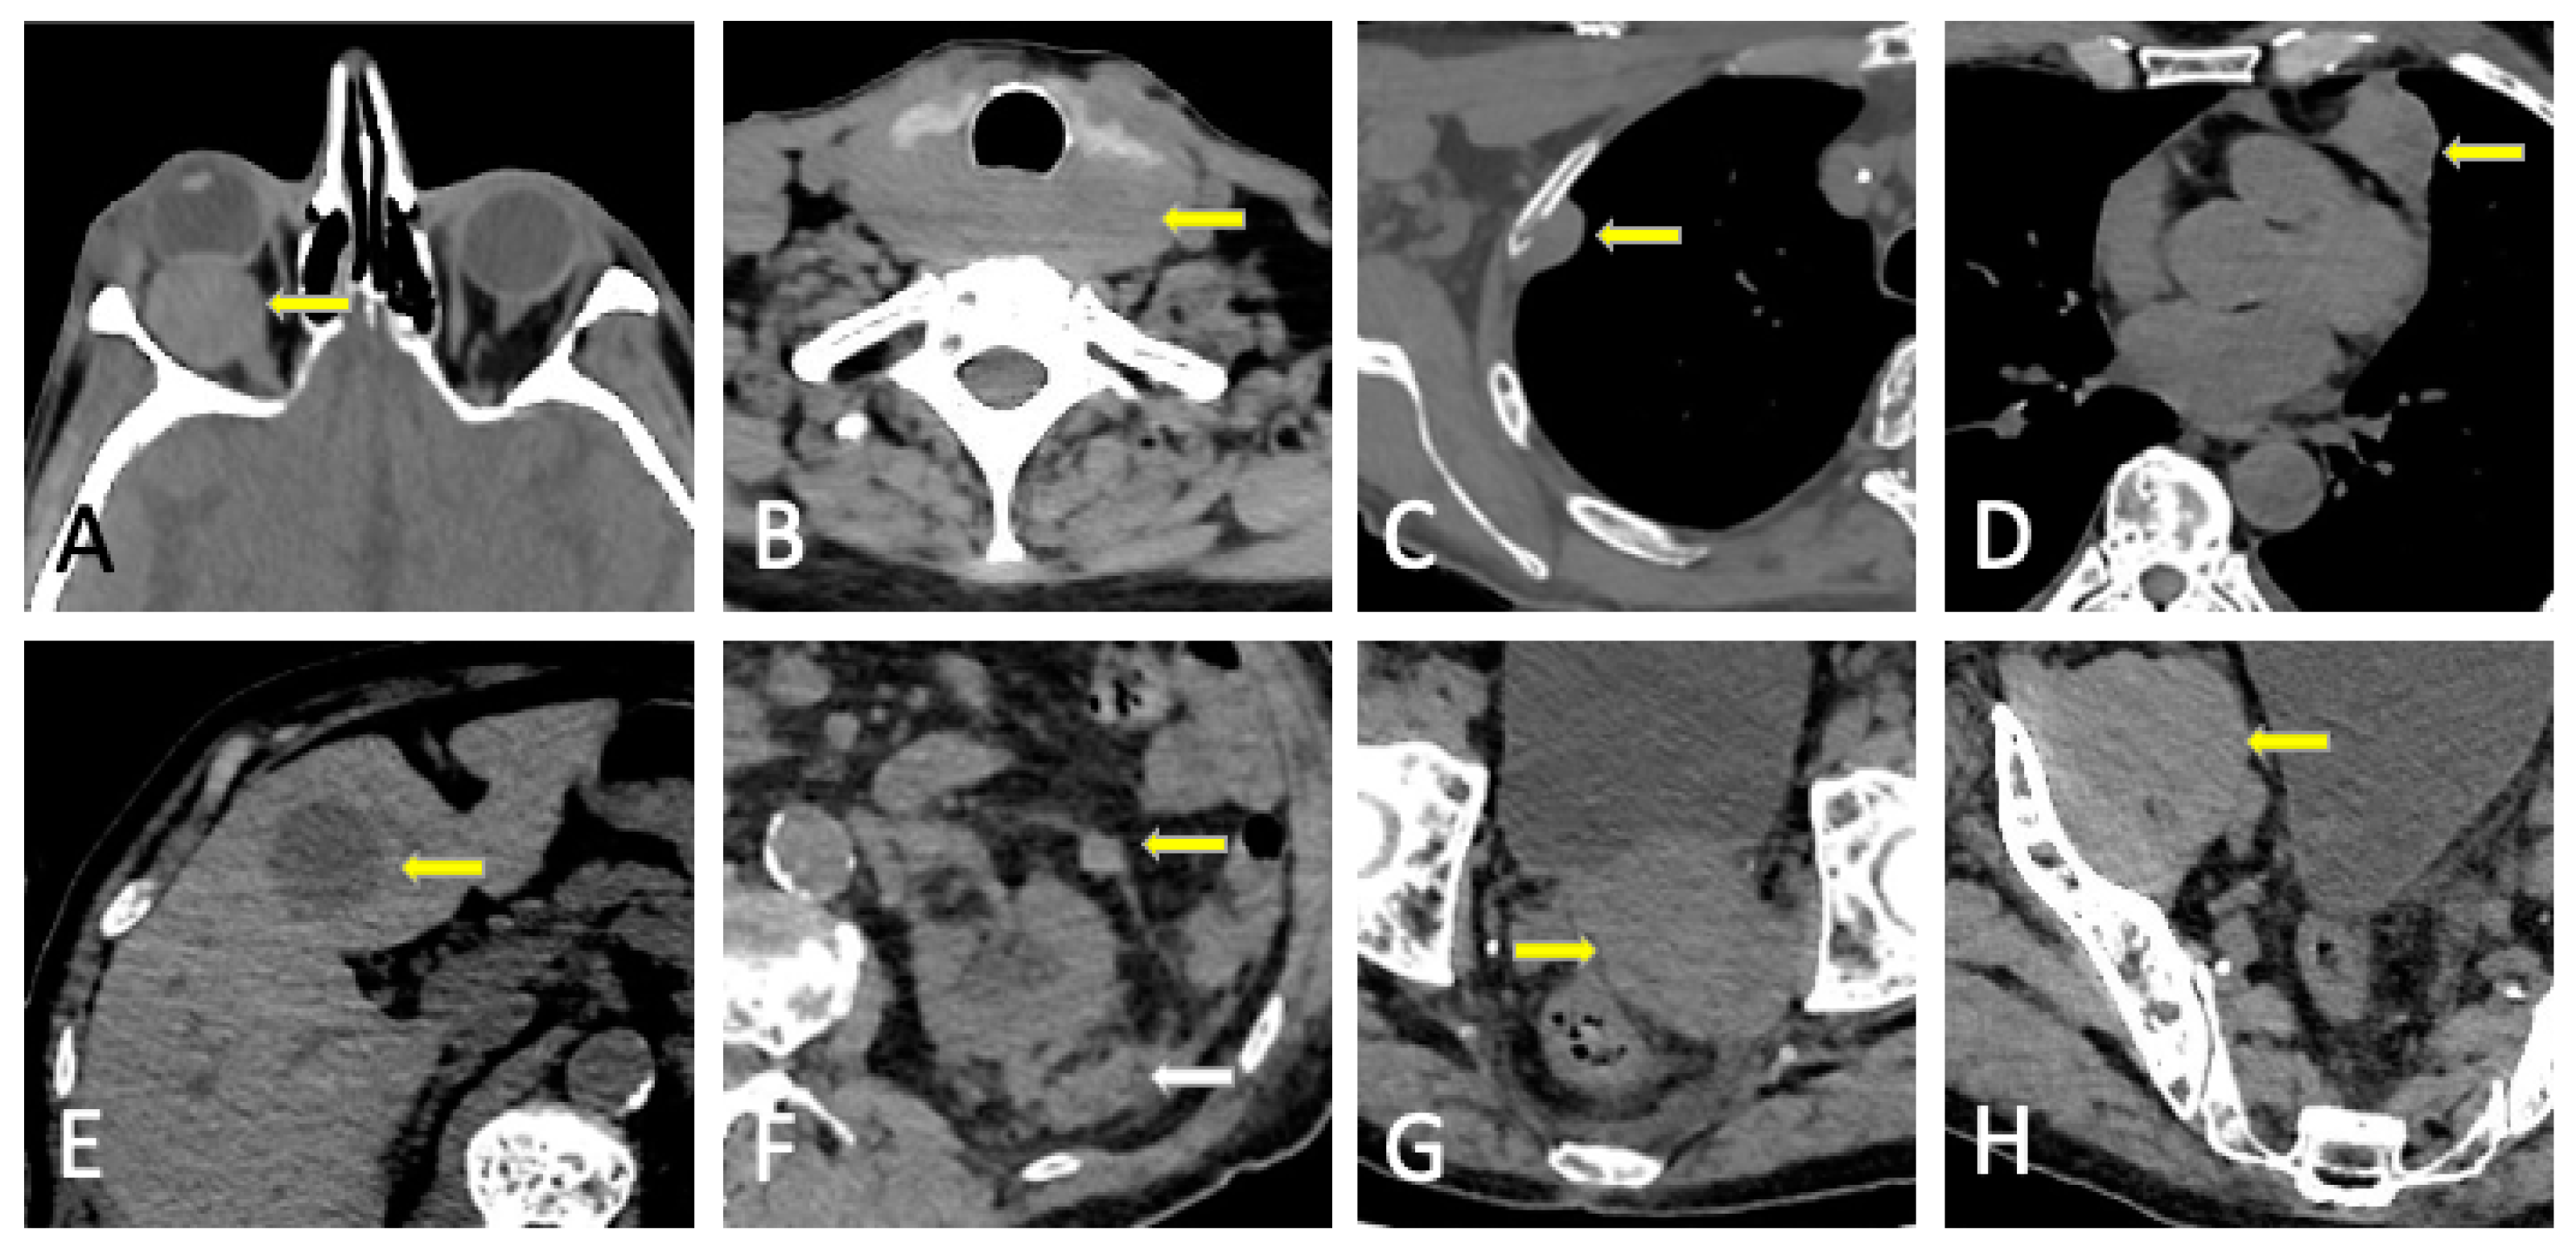

6. Plasmacytoma and Extramedullary MM